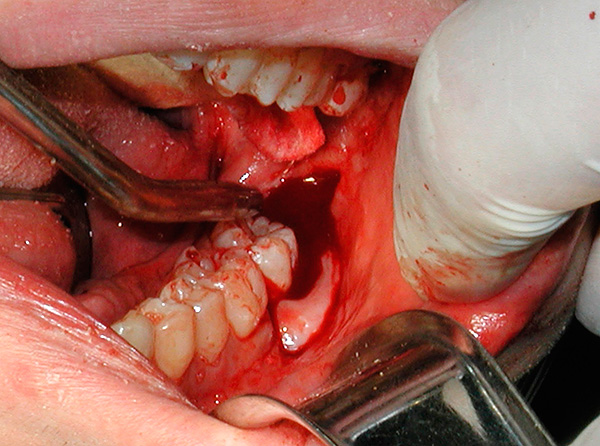

Va notato che, nonostante gli sforzi compiuti per ridurre la gravità dell'edema, può ancora apparire e causare disagio.Ciò è particolarmente frequente dopo la rimozione dei denti del giudizio ritardati sulla mascella inferiore. Il processo infiammatorio post-traumatico in connessione con l'anatomia e le peculiarità della disposizione dei denti del giudizio, nonostante gli sforzi compiuti dal medico e dal paziente, porta spesso alla comparsa di edema sufficientemente pronunciato.

L'immagine sotto mostra un dente del giudizio semi-rinforzato:

Non farti prendere dal panico subito. Di solito, l'edema raggiunge il massimo entro 2-3 giorni dopo la rimozione del dente del giudizio, e qui è importante controllare la condizione nel suo insieme e non solo un sintomo. Se c'è un grave deterioramento della salute (febbre a valori elevati, dolore insopportabile che non può essere fermato nemmeno dagli analgesici, suppurazione o sanguinamento dal buco), è necessario consultare immediatamente un medico.